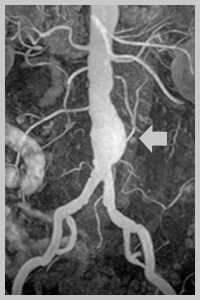

Аневризма брюшной аорты - это локальное выбухание или диффузное расширение стенки аорты в ее брюшном отделе. Аневризма брюшной аорты может протекать бессимптомно или обнаруживать себя пульсацией, болями в животе различной интенсивности, при разрыве аневризмы - клиникой внутрибрюшного кровотечения. Диагностика аневризмы включает проведение обзорной рентгенографии брюшной полости, УЗДГ брюшной аорты, рентгеноконтрастной ангиографии, КТ. Лечение аневризмы брюшной аорты исключительно хирургическое: открытая резекция аневризматического мешка с заменой иссеченной части синтетическим протезом либо эндопротезирование.

- Рентгеновская диагностика. Наиболее доступным методом диагностики аневризмы брюшной аорты служит обзорная рентгенография брюшной полости, позволяющая визуализировать тень аневризмы и кальциноз ее стенок. КТ или МСКТ брюшного отдела аорты позволяет получить изображение просвета аневризмы, кальциноза, расслоения, внутримешкового тромбоза; выявить угрозу разрыва или свершившийся разрыв. Кроме указанных методов, в диагностике аневризмы брюшной аорты применяются аортография, внутривенная урография.

- УЗИ аорты. В настоящее время в ангиологии широко используется УЗДГ, дуплексное сканирование брюшной аорты и ее ветвей. Точность ультразвукового выявления аневризмы брюшной аорты приближается к 100%. С помощью УЗИ определяется состояние стенки аорты, распространенность и локализация аневризмы, место разрыва.

К современным малотравматичным методам хирургии аневризмы брюшной аорты относится эндопротезирование аорты с помощью имплантируемого стент-графта. Хирургическая процедура выполняется в рентген-операционной через небольшой разрез в бедренной артерии; ход операции контролируется рентгенотелевидением. Установка стент-графта позволяет изолировать аневризматический мешок, предотвратив тем самым возможность его разрыва, и одновременно создает новый канал для кровотока. Преимуществами эндоваскулярного вмешательства являются минимальная травматичность, меньший риск развития послеоперационных осложнений, быстрое восстановление. Однако, по данным литературы, в 10% случаев отмечается дистальная миграция эндоваскулярных стентов.